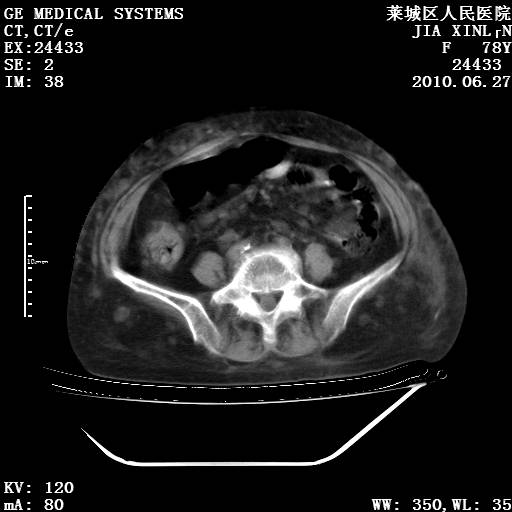

以下是引用胡宇在2010-7-2 19:11:00的发言:[br]神经纤维瘤的特点为:肿块呈多发性、数目不定,少的几个,多的可成百上千难以计数。小的如米粒,大的似拳头,甚至可达十数公斤以上。可松弛地悬挂于皮表,皱褶及松弛可致畸形明显。神经纤维瘤沿神经干的走向生长时呈念珠状,或蚯蚓块状形结节。此外神经纤维瘤皮肤可出现咖啡斑,大小不一,形如雀斑小点状,或大片状,分布与神经纤维瘤肿块的分布无关。肿瘤数目不多的患者,皮肤色素咖啡斑状沉着是纤维神经瘤的重要诊断之一。 本病多发于躯干,有时出现于四肢及面部,患者常合并许多疾病应予重视加以区别。 [br] [br] [br] [br]lyb999说 [br]